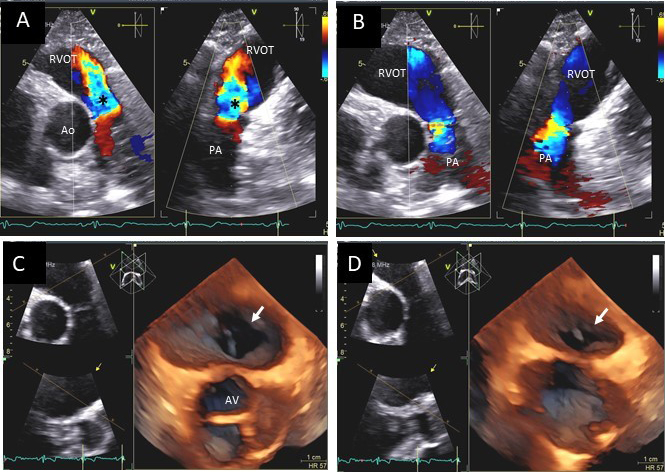

Fig. 11.Pulmonic valve regurgitation. (A) TTE basal short axis view

showing color Doppler of pulmonic valve (in the long axis view) and aortic valve

in the short axis view. There is severe pulmonic regurgitation as shown by a wide

diastolic jet in the RVOT occupying

Fig. 12.Pulmonic valve regurgitation and stenosis. Transthoracic echocardiographic images in a patient with carcinoid syndrome involving the pulmonic valve. Short axis biplane color Doppler views at the cardiac base showing severe pulmonic insufficiency (black asterisks - (A) and turbulent forward flow in systole due to pulmonic stenosis in (B). Three dimensional transthoracic views showing diffusely thickened and restricted pulmonic valve leaflets in systole (white arrow - (C)) and incomplete closure of the thickened pulmonic valve leaflets in diastole (white arrow - (D)) causing severe pulmonic regurgitation.